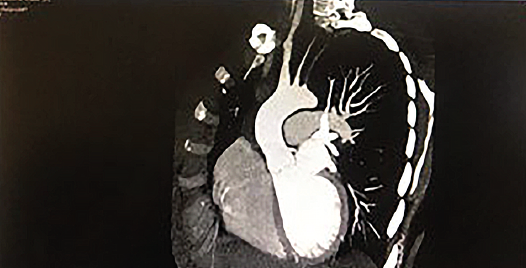

Triplex ultrasound scan of head and neck great vessels: a concentric thickening of the left common carotid artery intima-media, with a hemodynamically significant increase in the blood flow (Fig. 5), stenosis of the distal part of the left subclavian artery, signs of blood flow disturbance the internal jugular vein. CT angiography of the aorta with trunk branches showed similar changes (Fig. 6).

Fig. 6. CT angiography: stenosis of common carotid and subclavian arteries on the left